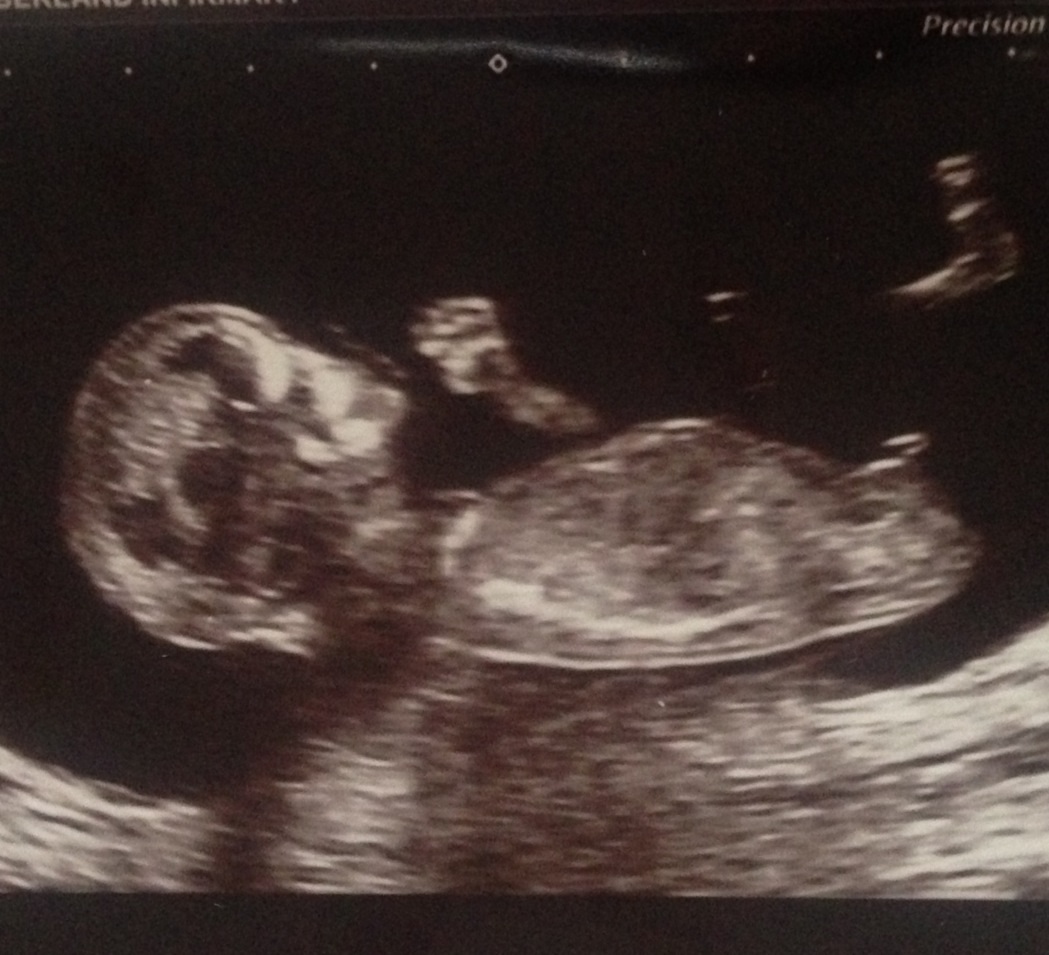

Very boyish nub - congrats!

Does any1 think girl? Ive been told the angle is too straight to be a boy :-/

I don't think it's parallel to the spine it's also stacked. When you look at the white nub line, there is a bulb above it. This indicates boy. I'd be surprised if it turn out to be a girl but it could happen of course.